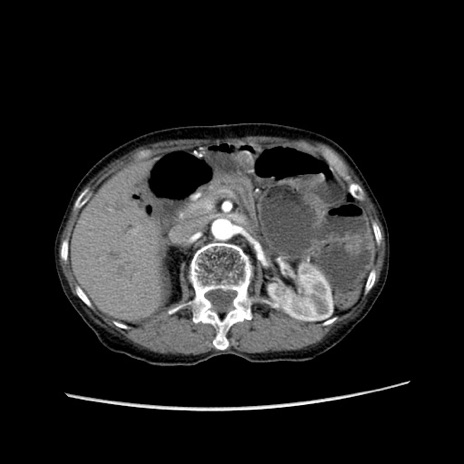

冠状断像

症例25(横断像)

【症例】80歳代女性

【主訴】胸のつかえ感

【現病歴】約9時間前に食後から胸のつかえた感じあり、嘔吐あり、来院。

【既往歴】胃癌(全摘)、胆摘、虫垂炎

【身体所見】心窩部に圧痛あり、反跳痛なし。

【データ】WBC 5700、CRP 0.05